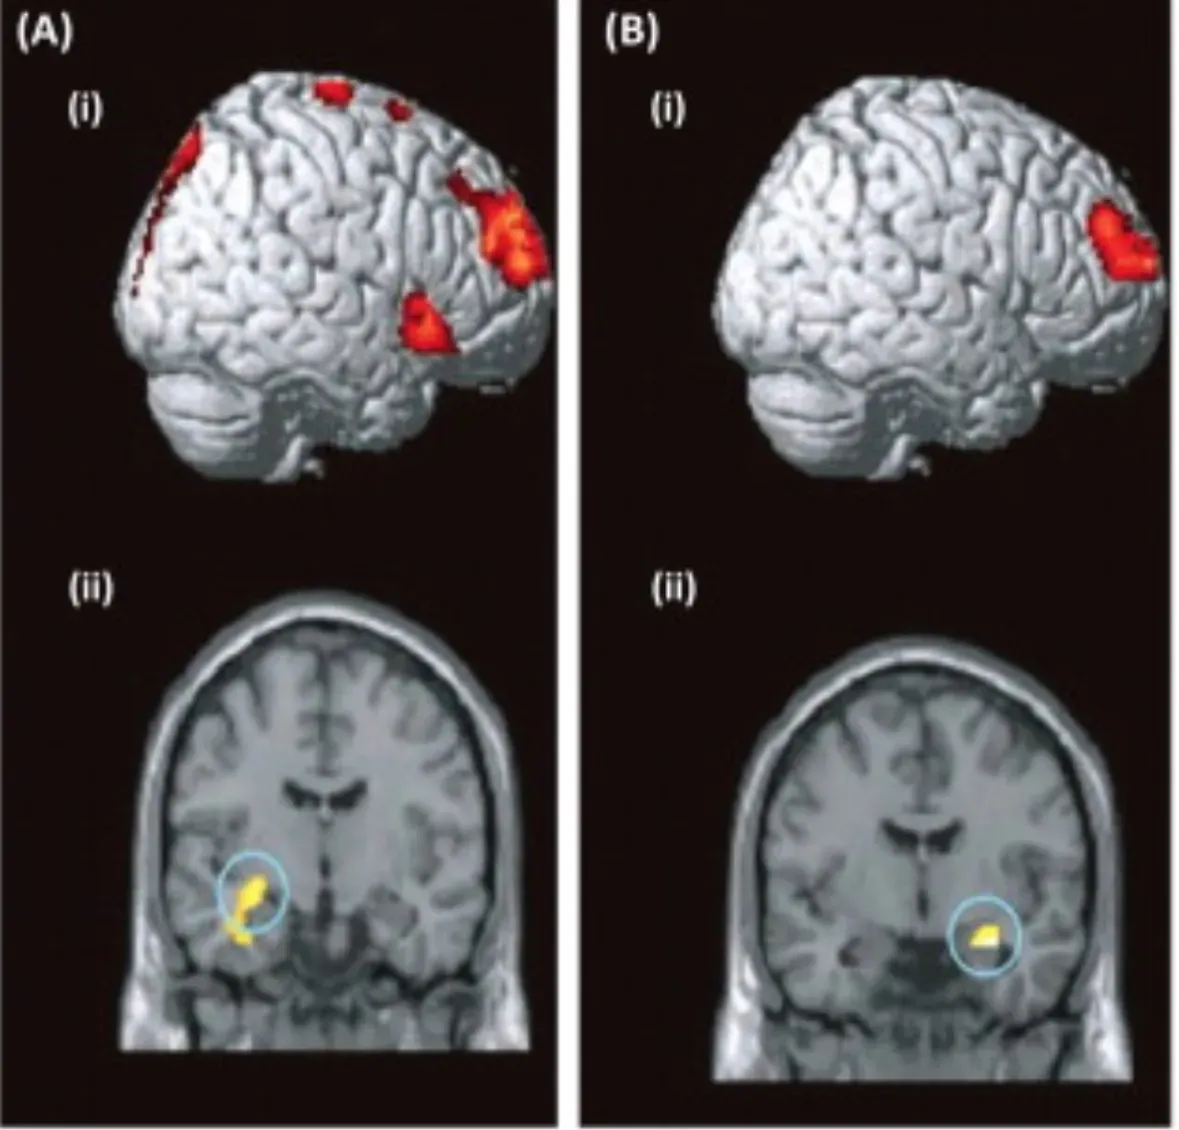

Your brain is already a master of integration, constantly blending information from your eyes, ears, skin, and inner body to create a single, seamless world. In synesthesia, researchers think some of that integration goes further than usual, likely because of extra connections or unusual communication between specific brain regions. For example, when you see letters and numbers as colors, the area that processes shapes and symbols is believed to “talk” more directly with the area that processes color, so the two experiences fuse together automatically.

Scientists also use brain imaging and clever reaction‑time experiments to peek under the hood. When you experience synesthetic colors or spatial layouts, your brain often activates regions that match those added sensations more strongly than in people without synesthesia. In speeded tasks, your performance can be helped or hindered by your synesthetic associations, which shows they are not just decorative ideas floating in the background. Together, these methods reveal that synesthesia behaves like a genuine perceptual feature of your mind, not a passing whim or a trick of language.